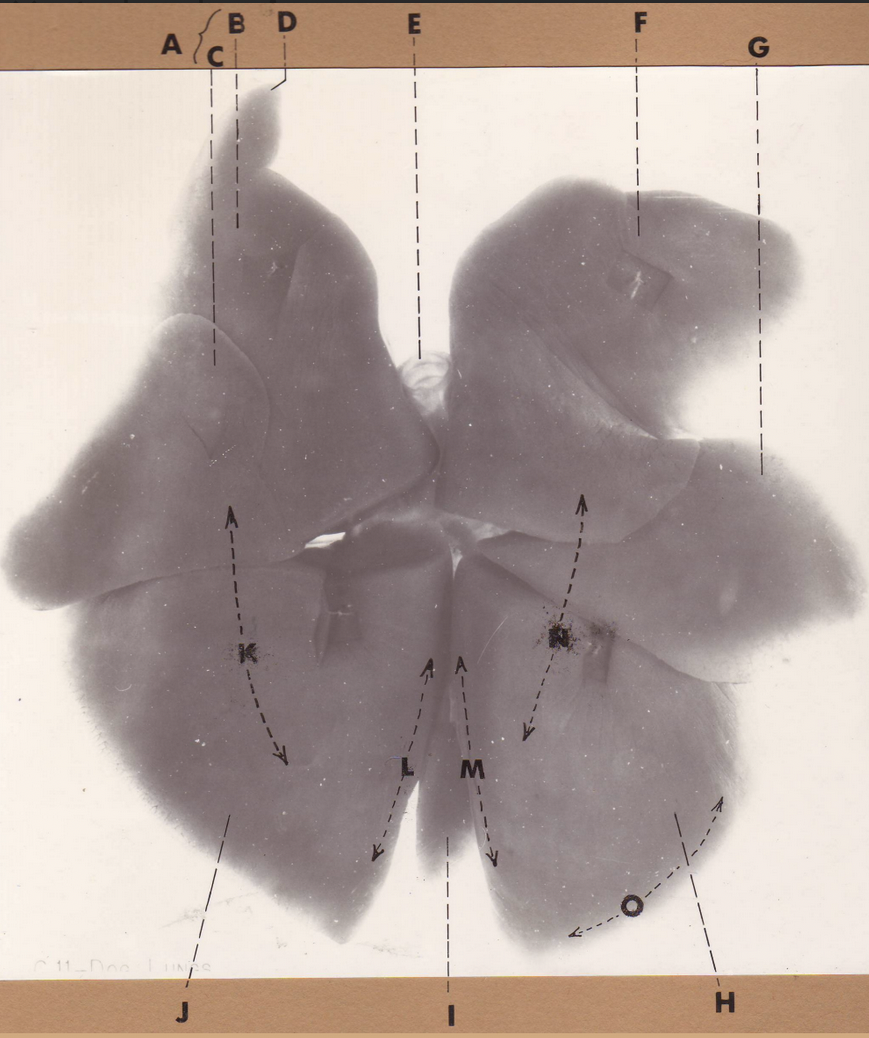

A

(dog lungs, dorsal)

L cranial lobe

B

(dog lungs, dorsal)

cranial segment, L cranial lobe

C

(dog lungs, dorsal)

caudal segment, L cranial lobe

D

(dog lungs, dorsal)

apex

E

(dog lungs, dorsal)

trachea

F

(dog lungs, dorsal)

R cranial lobe

G

(dog lungs, dorsal)

middle lobe

H

(dog lungs, dorsal)

R caudal lobe

I

(dog lungs, dorsal)

accessory lobe

J

(dog lungs, dorsal)

L caudal lobe